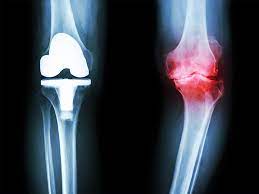

3. 수술적 치료

심각한 경우 수술이 필요할 수 있습니다. 관절 대체 수술이나 관절 연골 이식술 등이 선택될 수 있습니다.